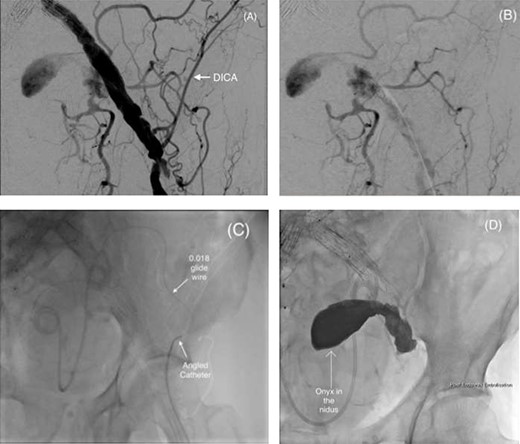

(A and B) Pre-embolization digital subtraction angiography (DSA) via a retrograde ipsilateral common femoral artery puncture demonstrating the left IIAA with inflow from the deep pelvic arteries including the DICA. (C) Microcatheter utilization to cannulate the aneurysm nidus with an angled catheter over an 0.018 hydrophilic Glidewire® to access the DICA. (D) Onyx™ successfully injected into the IIAA nidus.